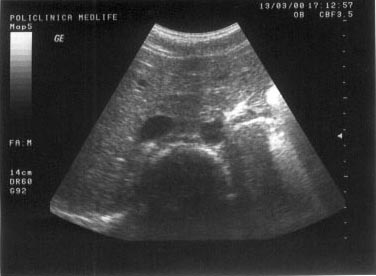

Imaginea "in cocarda"

Imaginea "in cocarda" este o imagine rotunda, are centrul hiper/izoecogen, inconjurat de o arie circulara hipoecogena.

Exemplu:

tumorile maligne hepatice primitive sau metastatice (haloul periferic hipoecogen este generat de necrozele tumorale).

Imaginea mixta

Imaginea mixta, neomogena este generata de alternanta de arii hipo si hiperecogene.

Exemple:

necroza sau hemoragia intratumorala;

abcesul hepatic.

Figura

13. Ovarul st`ng este ]nlocuit de o formaiune complex[, transsonic[ =i

solid[. Partea solid[ ]n proporie de 40%, cu ecostructura hiperecogen[

este dispus[ sub forma de prelungiri papilifere cu contur neregulat =i

prezint[ ]n interior c`teva mici zone transsonice (posibil arii de

necroz[). Aspectul sugereaz[ chistadenocarcinom ovarian.